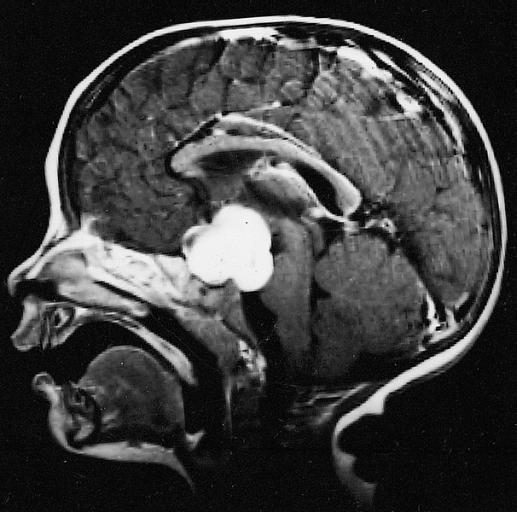

毛细胞星形细胞瘤 是一种生长缓慢、边界较清的囊性星形肿瘤,是一种 良性胶质瘤 病理分型,WHO I级。 发病特点 毛细胞星形细胞瘤常发生于儿童和年轻人...

小儿丘脑肿瘤常被认为是无法手术的。但是,现代显微外科技术以及神经影像学的改进使得能够进行准确的术前计划,可以以更顺利的方式进行切除...